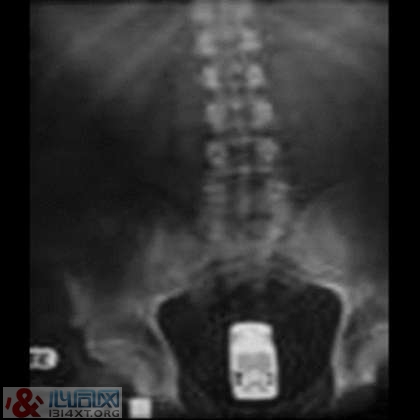

10. 凝结成骨盆腔形状的水泥